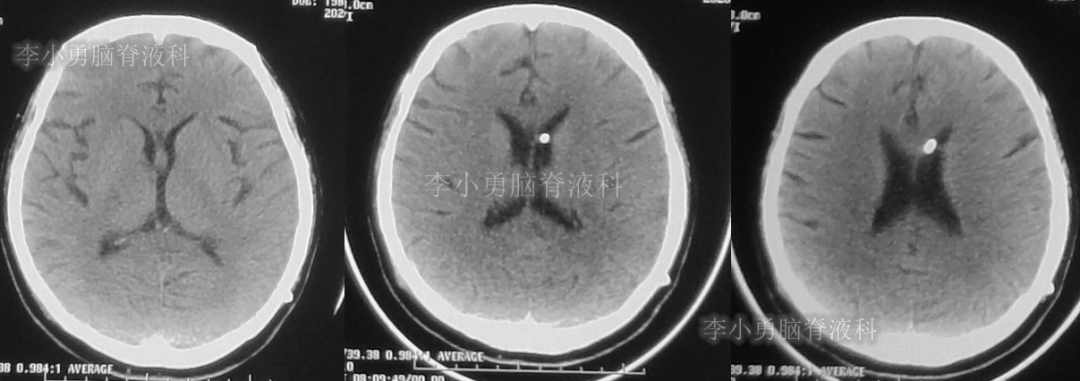

入院时(2020年2月21日)头颅CT(图-22)见脑室缩小,呈裂隙状。

图-22:2020年2月21日头颅CT